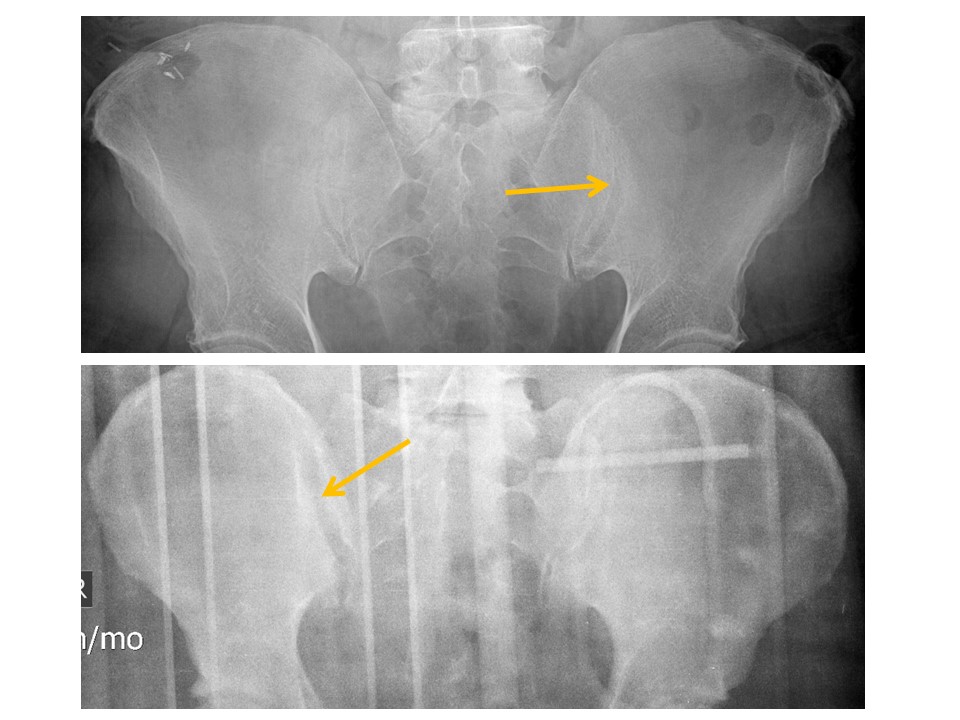

IMAGE QUALITY

Portions of the patient’s anatomy are excluded from the field of view [Yes/No]

There are external structures overlying the patient’s pelvis, such as a backboard. [Yes/No]

The image is rotated. [Yes/No]

PUBIC SYMPHYSIS and RAMI

The pubic symphysis is widened or vertically incongruent. [Yes/No]